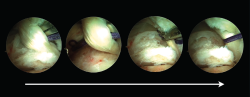

Una vez el tendón está dentro del túnel, debe ser bloqueado con un tornillo interferencial o de biotenodesis. Idealmente, el tornillo debe ser del mismo diámetro que el túnel calcáneo realizado. El tornillo se introduce guiado con un nitinol para que tome una dirección correcta. Con el tobillo en flexión plantar y traccionando de las suturas para tensar el tendón FHL, se introduce el tornillo bajo control endoscópico directo (Figura 7).

Figura 7. Visión final de la transferencia del tendón flexor hallucis longus (FHL). Izquierda: visión proximal; derecha: visión distal con visualización del tendón del FHL correctamente fijado al calcáneo con un tornillo interferencial.